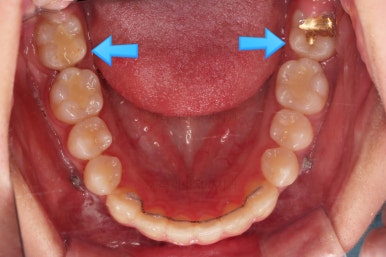

부산교정 키다리아저씨치과에 처음 내원하셨을 당시의 입안 모습과 X-ray 사진입니다.

맨 안쪽 치아가 마치 사랑니인 것처럼 누워있고 애매하게 나와있었어요.

문제는 해당 치아가 썩었다는건데, 기울어있는 치아를 제대로 치료할 방법은 사실상 없죠. 앞에 치아에 가려진 부분이 썩었으니깐요.

저대로 계속 놔두게 되면 누워있는 어금니 + 앞쪽 어금니 두 개 다 상해서 결국 뽑아야 되는 상황까지 벌어질 수 있어요. 그것도 양쪽으로 모두 다요.